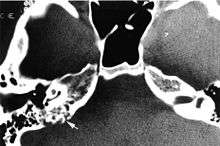

Imaging studies help to identify the tumor and the specific anatomic site of involvement. Magnetic resonance images show a hyperintensity (hypervascularity) of a heterogeneous mass by T1 weighted images. Computed tomography shows a multilocular, lytic destructive temporal bone mass, centered within the endolymphatic sac (between internal auditory canal and sigmoid sinus).[1][5][6]